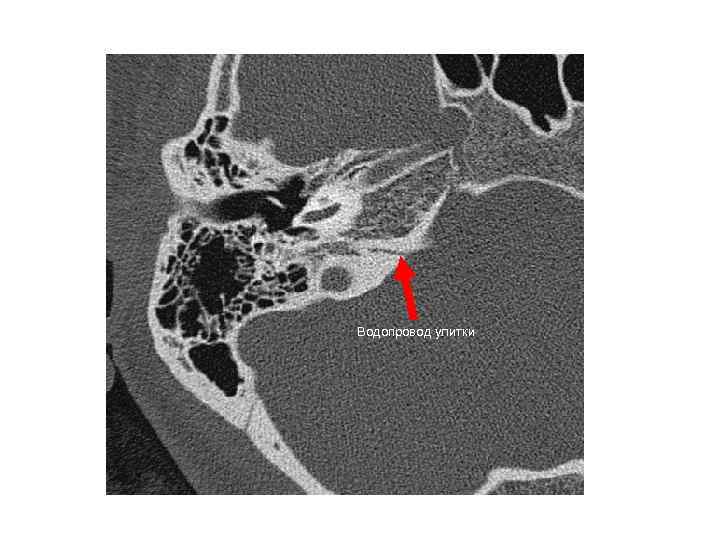

Водопровод улитки Водопровод улитки